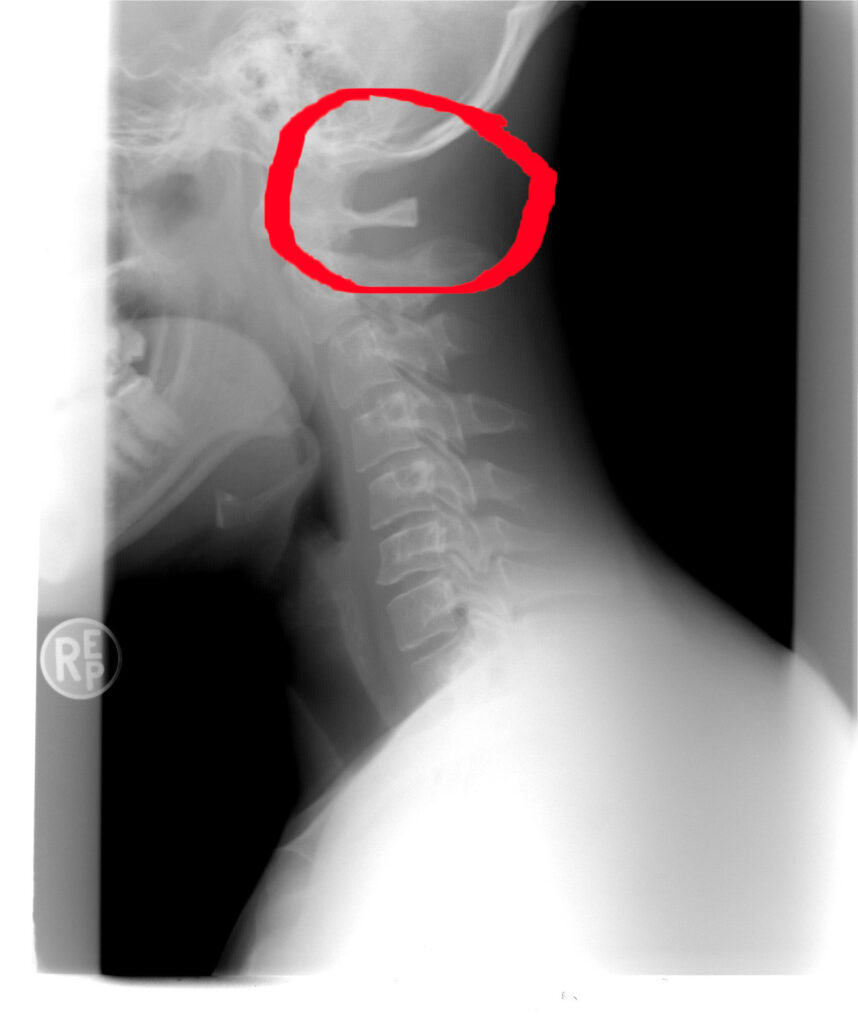

6. The Base of the Skull: The Center of Control

cervical spine

There’s an important place where the spine meets the skull, right at the base of the neck.

Energetically, this area relates to control.